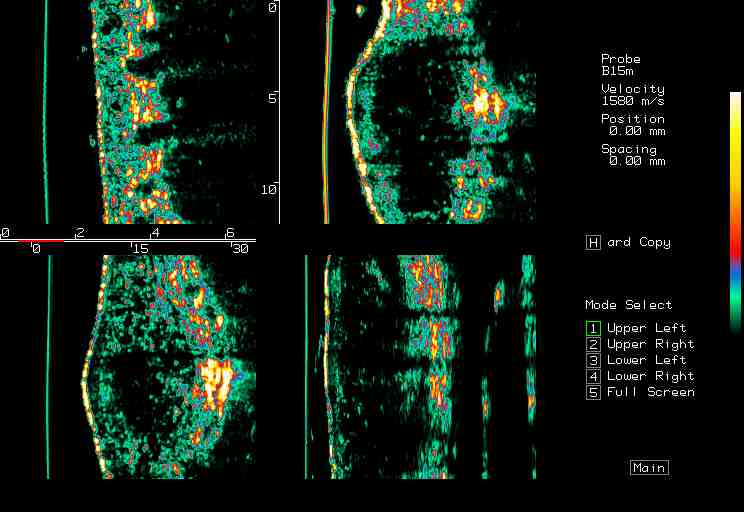

20 MHz 2D images

20 MHz 3D images

| Misc. |  Cellulite, arm |

Microdialysis tube |

Intradermal nevus |

Highlight. intrad. nevus |